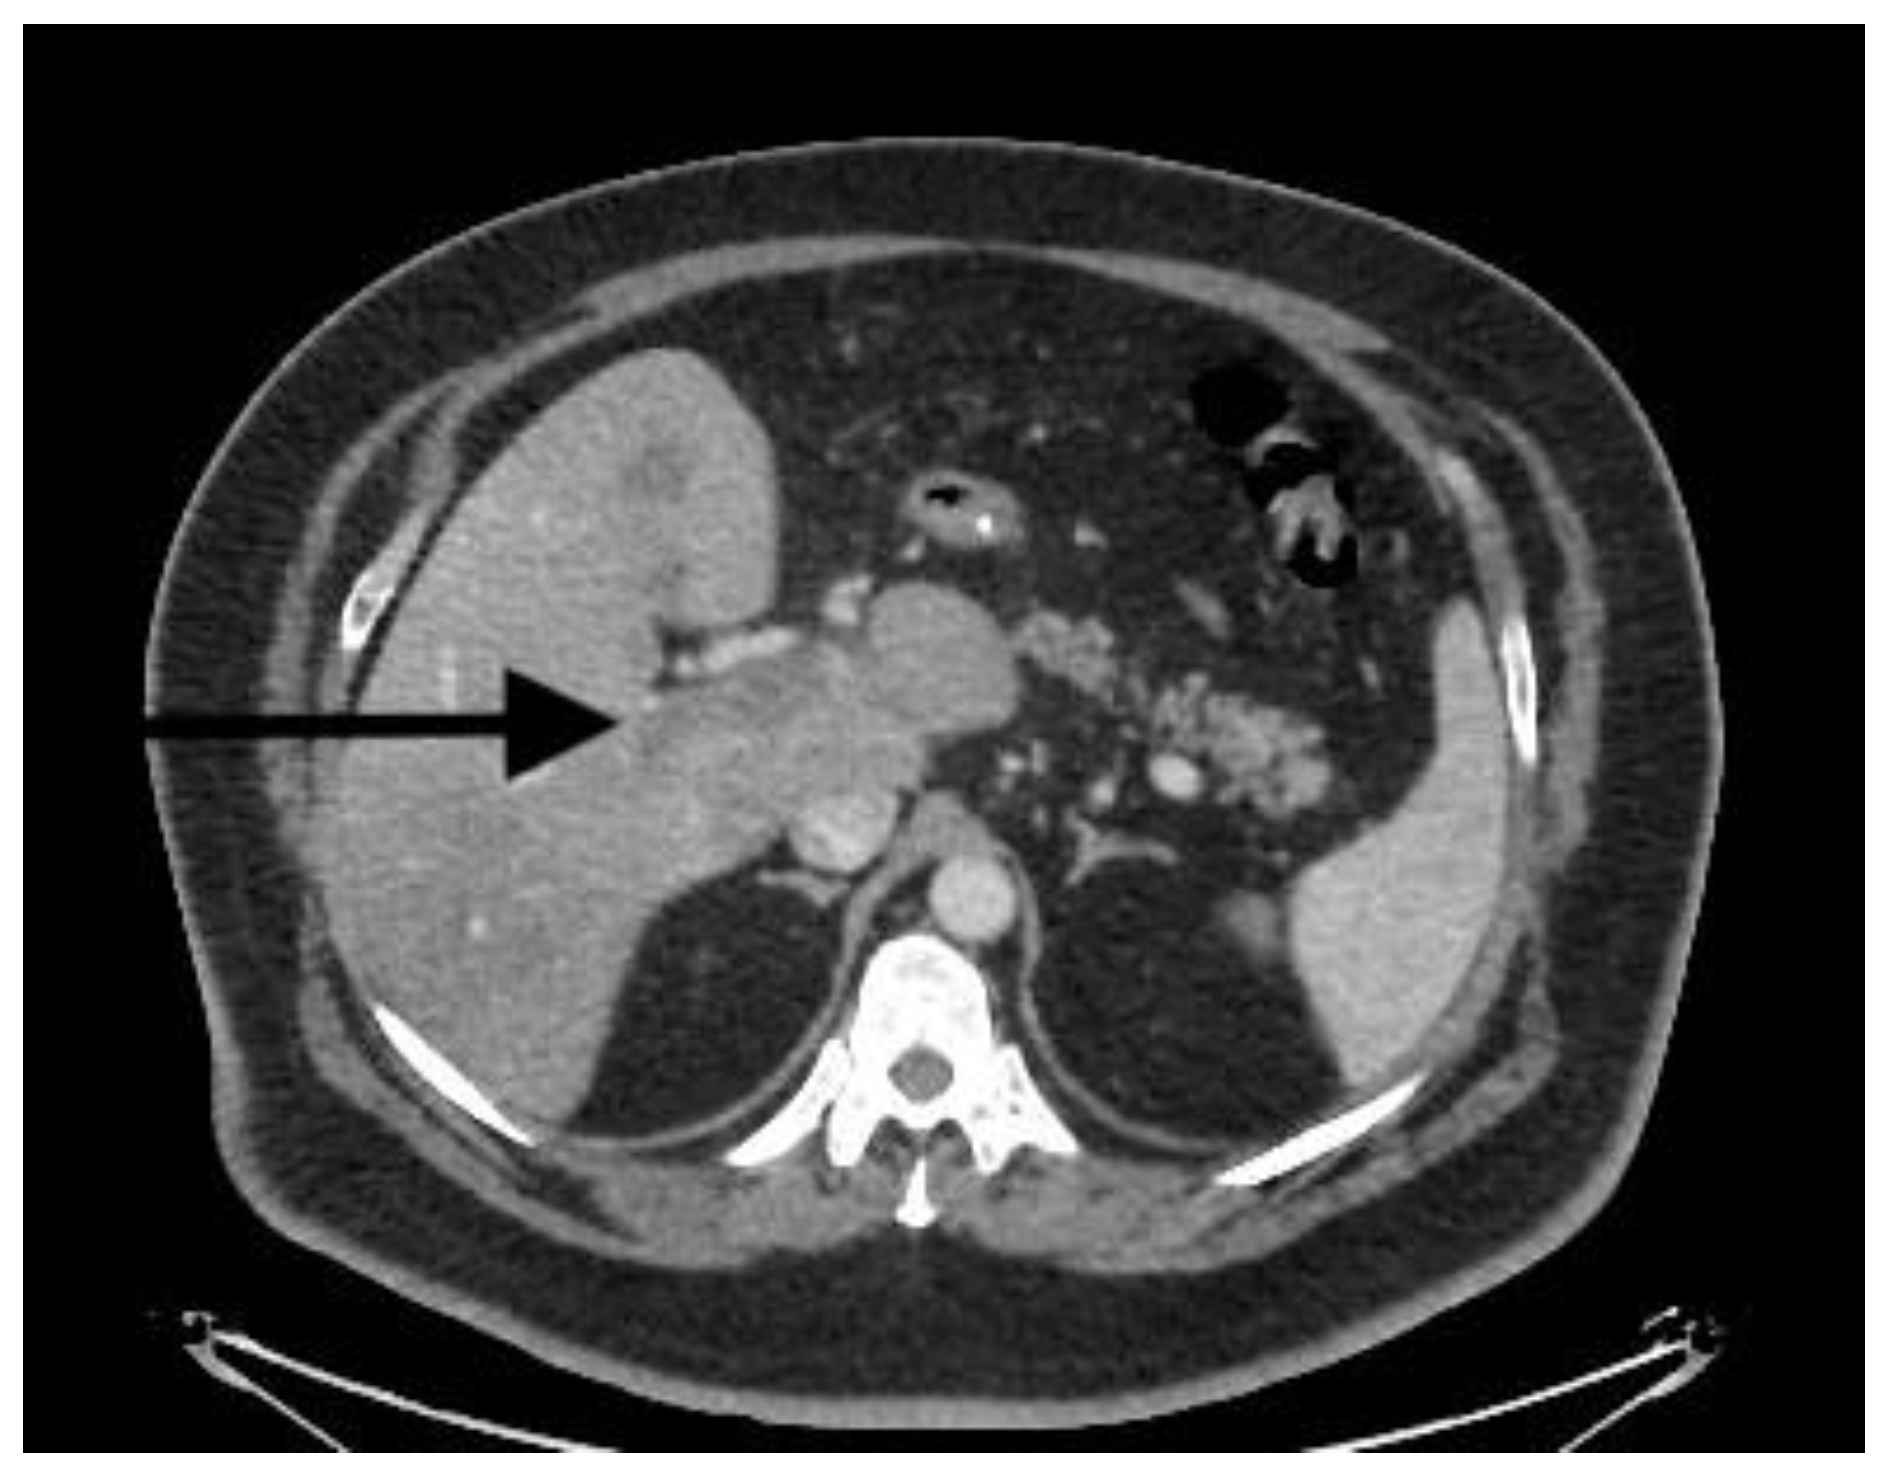

| Doppler ultrasound | Partial PVT | Partial PVT | Complete PVT | Partial PVT |

| CT scan | Nonocclusive PVT, posterior right branch, and partial superior mesenteric vein | Nonocclusive PVT, right branch, and partial superior mesenteric vein | Extensive occlusive, portal, splenic, and mesenteric thrombosis; ascites evidence of small-bowel hypoperfusion | Partial PVT |